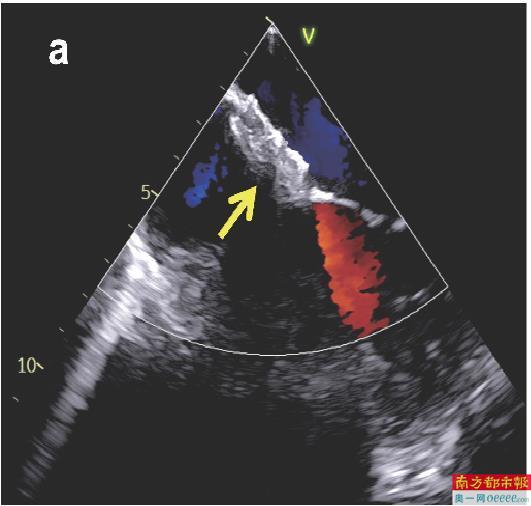

(b)可降解封堵器植入后X线影像。

(c)传统金属封堵器植入后X线影像。箭头所示为封堵器,在X线影像上可降解封堵器几乎不可见。